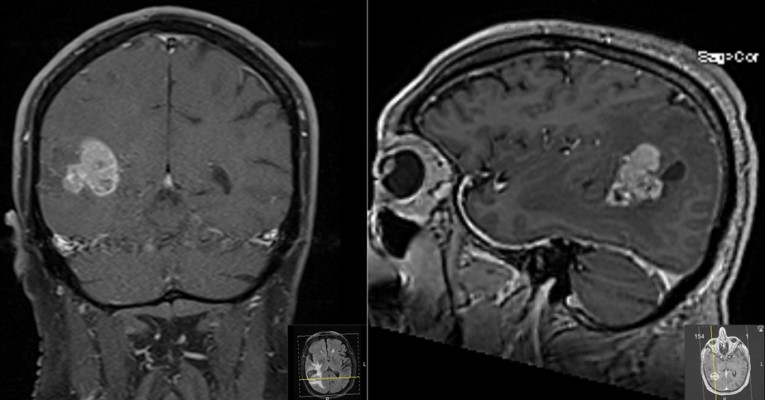

This is a 69 year old male with a known history of renal cell carcinoma who presented with cognitive decline and a neck mass.He had memory issues which were attributed to chemotherapy. He also was having new headaches. The neck mass was due to an infection. Neurologic examination was relatively unremarkable.

- Pre-Op